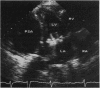

The development of a left ventricular pseudoaneurysm is a rare complication of heart surgery. Until recently it has been impossible to detect without an angiographic study of the left ventricle. A combination of cross sectional and Doppler ultrasound studies led to the correct diagnosis in two patients with left ventricular pseudoaneurysms after mitral valve replacement. Cross sectional echocardiography showed a posterolateral echo-free space confined only by the pericardium and communicating with the left ventricle through a defect in the ventricular wall, and Doppler echocardiography confirmed the presence of blood flow in this cavity. This Doppler finding is critical if the perforation is too small to be identified reliably by cross sectional imaging. Surgical repair of the pseudoaneurysm can be undertaken without invasive studies if the echocardiographic findings are unequivocal and there is no reason to suspect the integrity of the circumflex coronary artery.